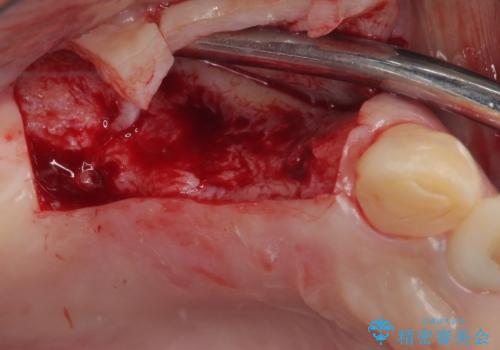

臼歯はもはや咬み合わせに寄与していない状態であり、3歯を抜去してインプラント2本埋入によるブリッジ補綴を計画しました。

臼歯部は前歯以上に炎症が酷く、抜歯即時埋入不可と判断されましたが、従来法よりは短期間で終えることができました。